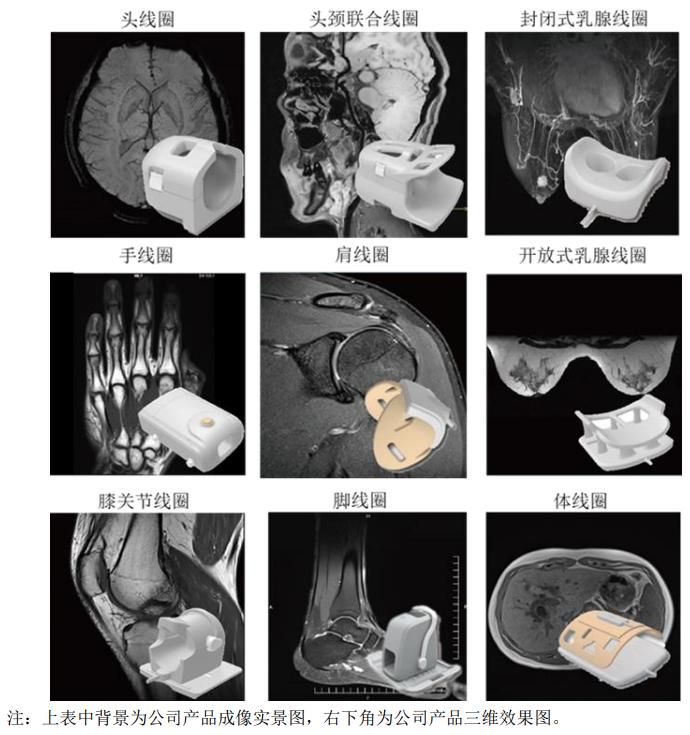

普通型射频探测器主要用于人体医学成像,包括常见的头、头颈联合、乳腺、肩、手、 膝关节、脚、体线圈等。